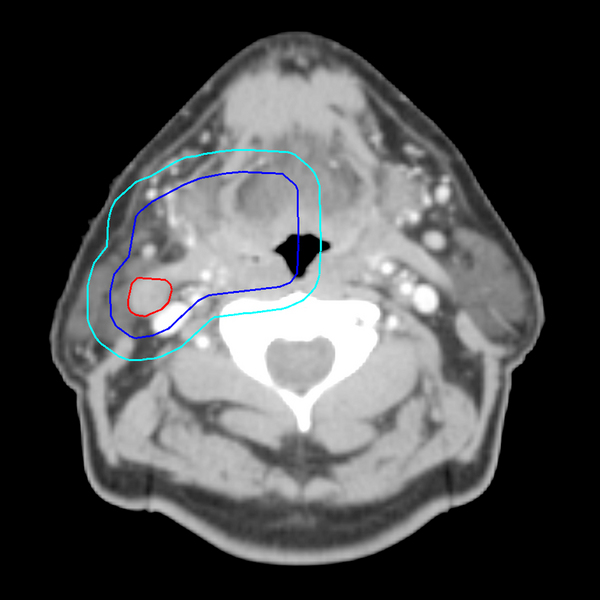

The following “real world” examples from actual patient cases illustrate some of the volumes previously defined.

In this image, the red line delineates the GTV (Gross Tumor Volume), the dark blue line the CTV (Clinical Target Volume), and the light blue line the PTV (Planning Target Volume).